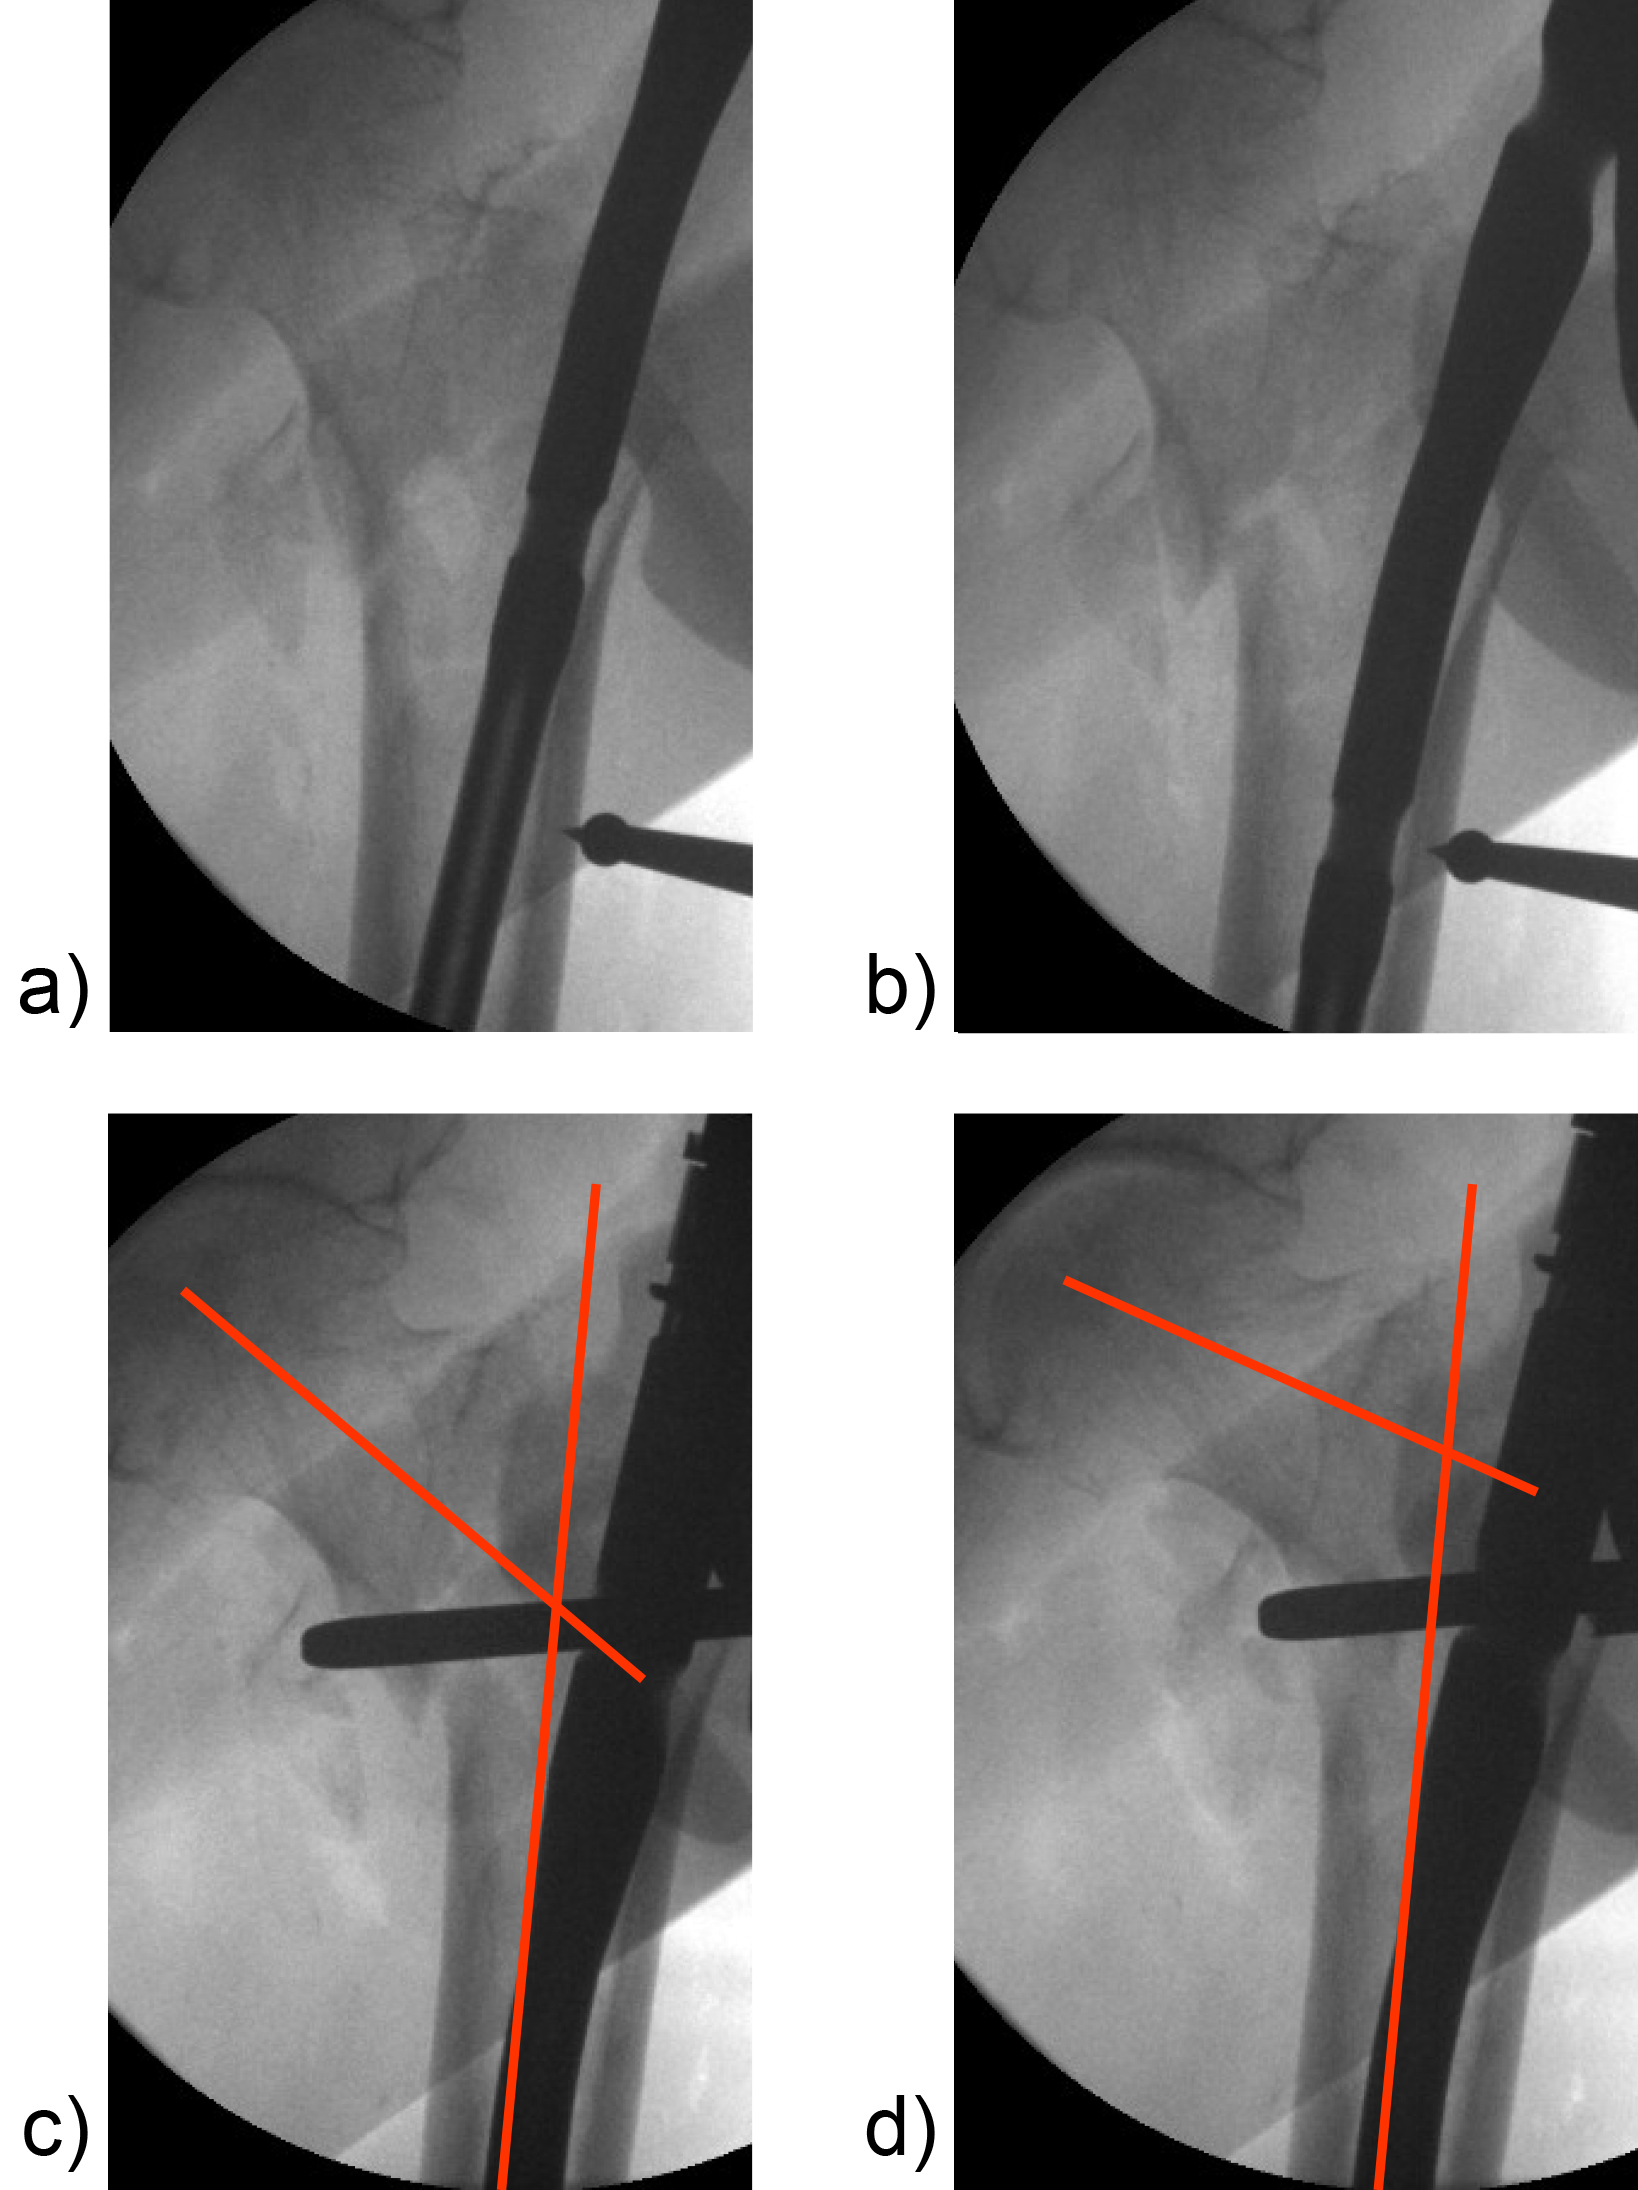

Hollow reamer

When the TFN-Advanced proximal femoral nailing system was launched in 2015, flexible and solid drill bits were offered to prepare the entry path of the nail. When fracture lines are located in the area of the intended nail insertion point, fracture fragments can be pushed apart when introducing these drill bits through the fracture lines causing a varus malreduction of the head-neck fragment. In order to avoid this clinical problem, an optional hollow reamer has been developed (Fig 5).

When using the hollow reamer, fracture fragments are not displaced because the instrument facilitates the removal of a cylindrical bone plug from the insertion area (Fig 6) without causing radial displacement forces to the surrounding bone.